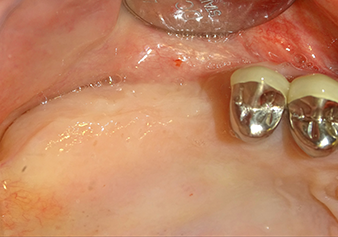

A 49-year-old female patient, a non-smoker and with nothing remarkable in her general medical history, was referred to our oral surgery practice for surgical extraction of tooth 16 and subsequent implantation. After the extraction, the patient experienced mild sinusitis trouble with the resultthat we initially waited six months before carrying out the measure. The residual bone height at the planned implant position measured 3-4 mm (Fig. 1 and 2).

Implantation and prosthetic restoration

To move the augmentation material in the direction of the maxillary sinus atraumatically, the implant was inserted very slowly by hand (Fig. 9). In the process, the membrane was pushed in the cranial direction once again. After two months, the surgical site healed without irritation. Six months later, the x-ray check showed a significant increase in opacity as an indication of ossification (Fig. 10). The prosthetic restoration was carried out with a metal-ceramic crown.